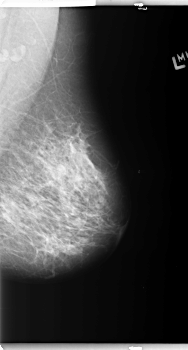

B_3148_1.RIGHT_MLO

RIGHT_MLO LINES 5960 PIXELS_PER_LINE 3680 BITS_PER_PIXEL 12 RESOLUTION 50 OVERLAY

FILE: B_3148_1.RIGHT_MLO.OVERLAY

TOTAL_ABNORMALITIES 2

ABNORMALITY 1

LESION_TYPE CALCIFICATION TYPE AMORPHOUS-PLEOMORPHIC DISTRIBUTION CLUSTERED

ASSESSMENT 4

SUBTLETY 2

PATHOLOGY BENIGN

ABNORMALITY 2